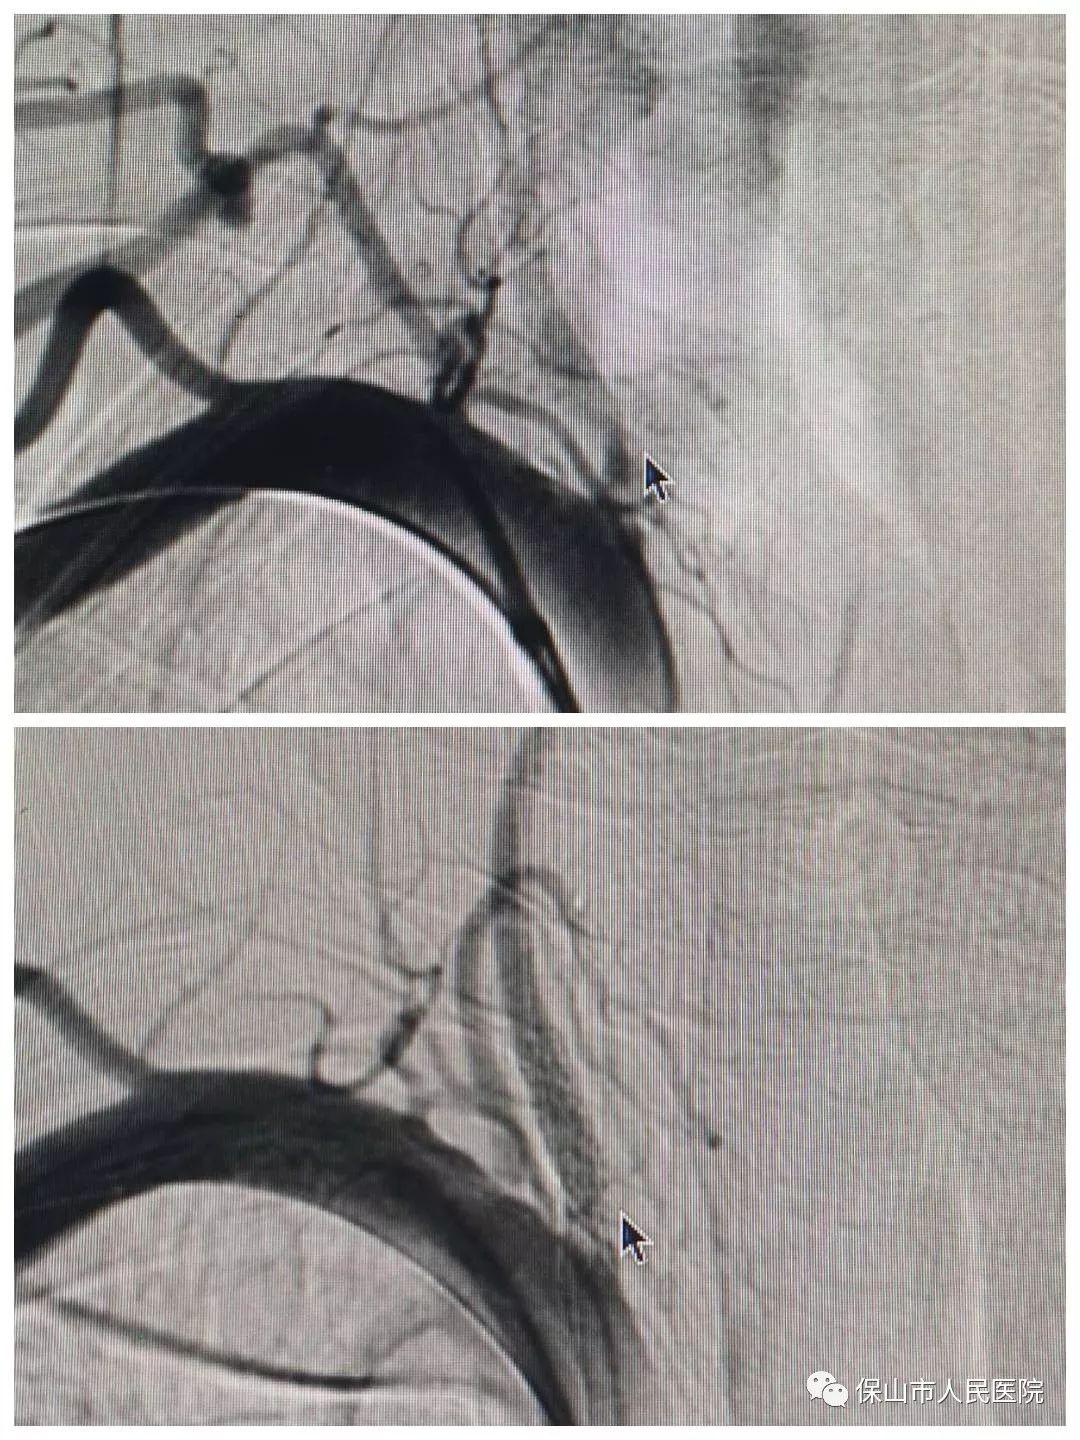

圖中箭頭指示的地方就是狹窄部位。左側(ce) 椎動脈於(yu) 開口處狹窄,狹窄程度在90%以上。

這樣左右對比更直觀,右側(ce) 椎動脈開口是正常的,術中造影證實左側(ce) 椎動脈開口重度狹窄,與(yu) 術前診斷一致。正是這個(ge) 狹窄,導致患者左側(ce) 椎動脈內(nei) 血流速度較慢,一定程度上影響了供血,所以患者才會(hui) 出現短暫性意識模糊和反複頭暈的症狀,因此,必須將狹窄部位重新開通。